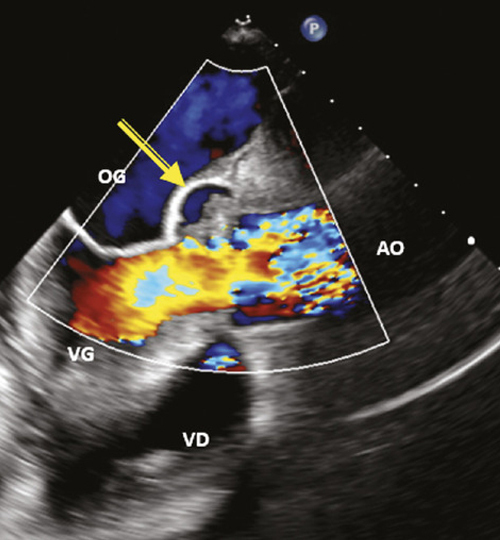

Bernard A, Chane-Sone N, Dion F, et al. Endocardites infectieuses : démarche diagnostique. Rev Prat 2024 ;74(6) ;639 - 45.